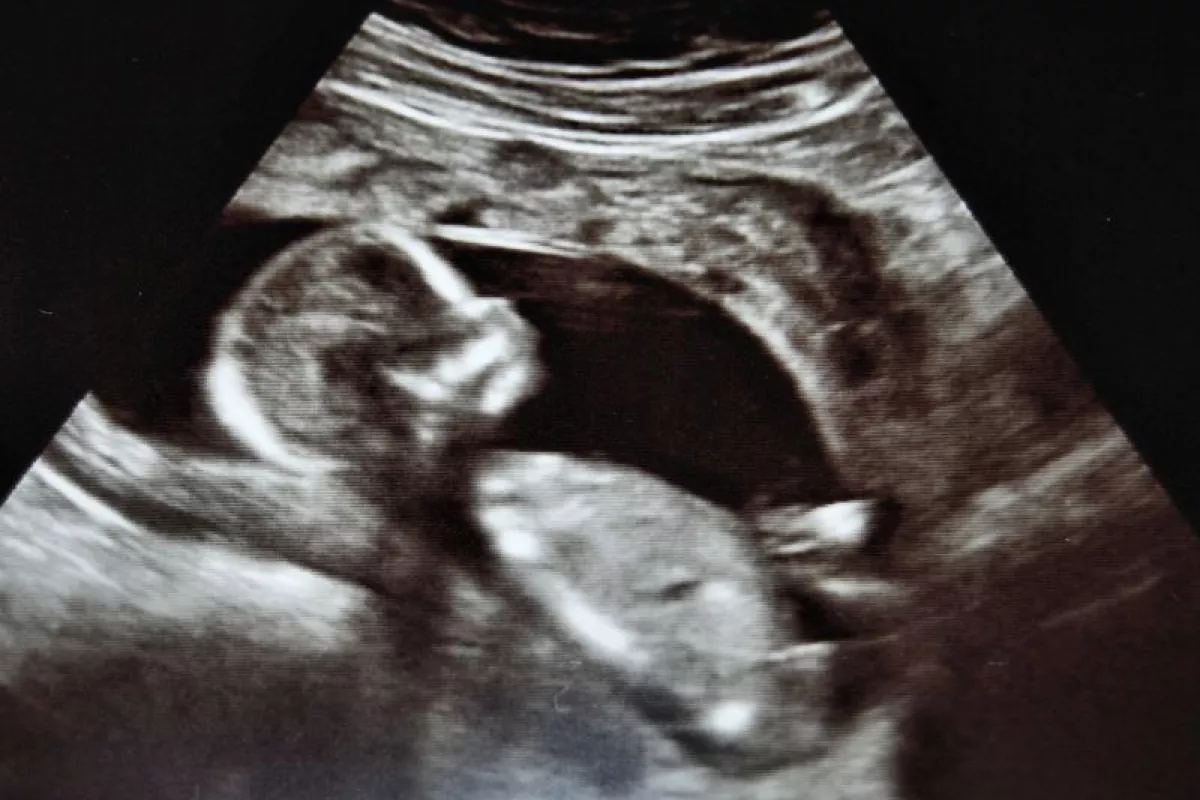

A newly developed acoustic rectifier could improve the image quality of sonograms (Photo: myllissa via Flickr)

Sonography, or ultrasound imaging, is commonly used for diagnostic and therapeutic applications – the best-known example being photos and videos of developing fetuses that expectant parents excitedly wave around. Because ultrasound relies on sound waves being sent into the body and then reflected back to create the image, the interference creating by these waves meeting causes some degradation of image brightness and resolution. In order to enable stronger, sharper medical imaging, scientists at Nanjing University in China have developed an "acoustic rectifier" that forces sound waves to travel in only one direction.